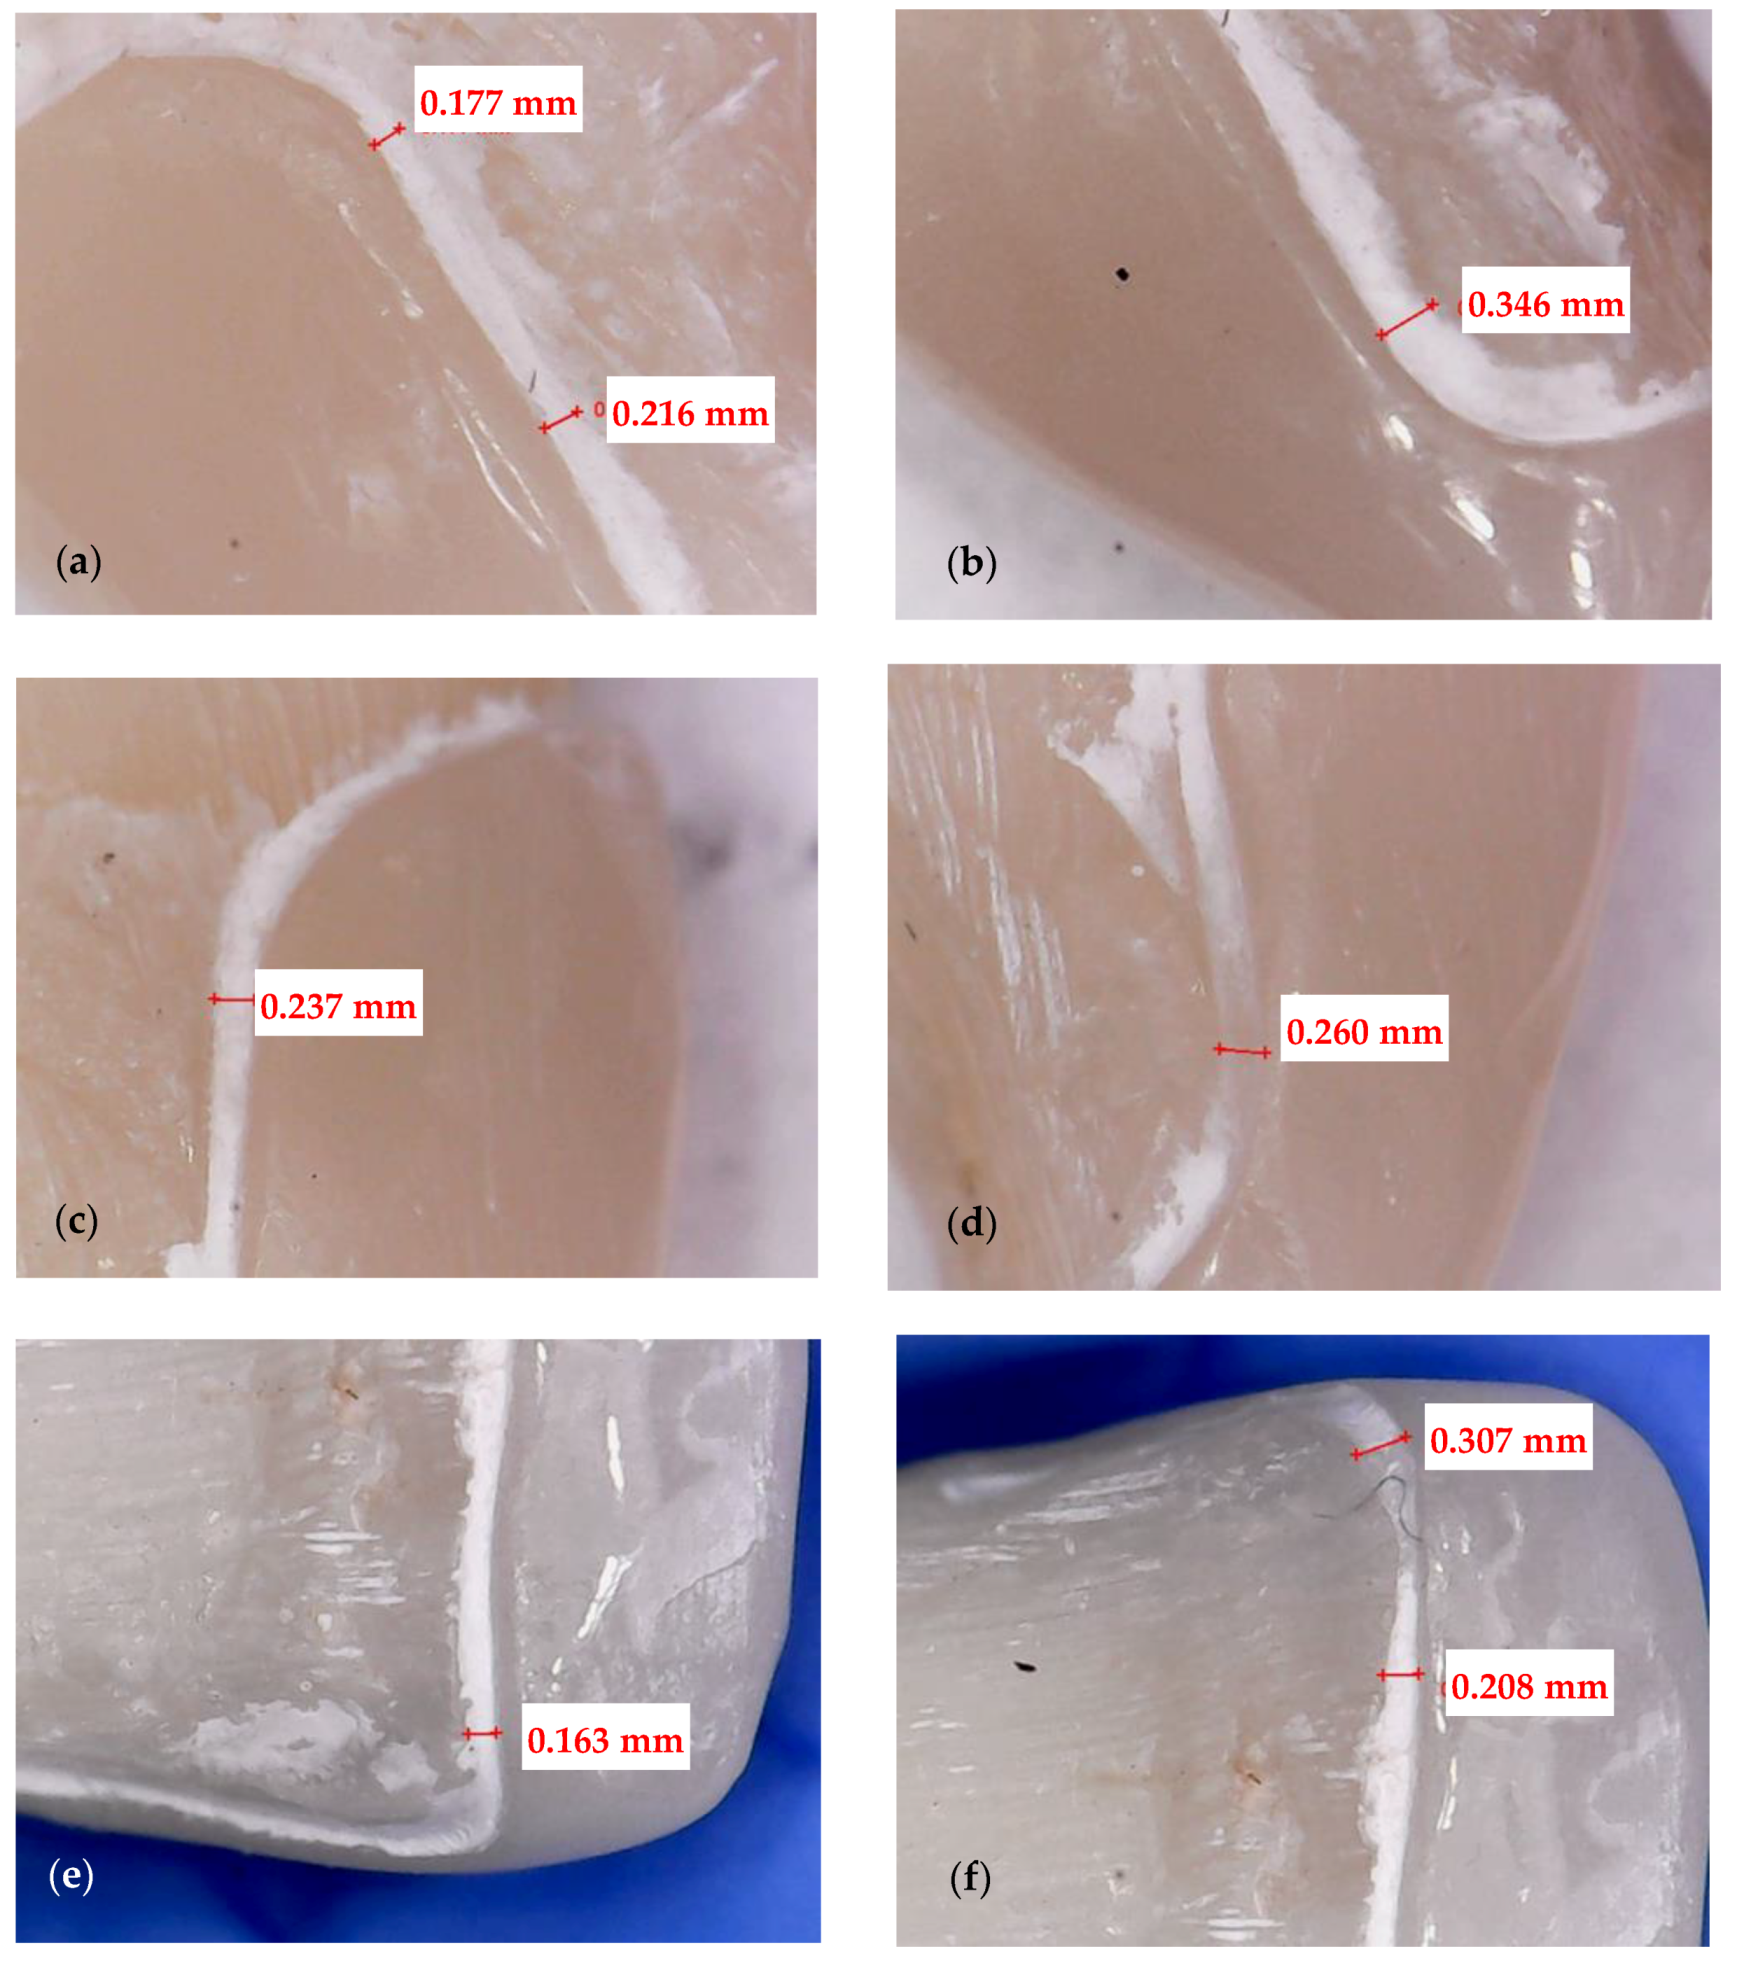

2.3. Optical Microscopy

3.1. Optical Microscopy

- Crenelated (CR) ceramic dental veneers, with their marginal sinusoidal contour, displayed a higher marginal adaptation (60 μm) than the conventional (CO) (with linear margins) veneers (230 μm).

- Micro-CT proved to be reliable and precise to evaluate the internal adaptation of the restorations, as well as the porosities localized in the luting cement. It has the advantage of providing 3D information on the entire volume of dental cement (i.e., the interface between dental support and veneers). The more common and accessible tool, optical microscopy, provided valuable data regarding the marginal adaptation, with a good agreement with the micro-CT results, but cannot evaluate internal adaptation.